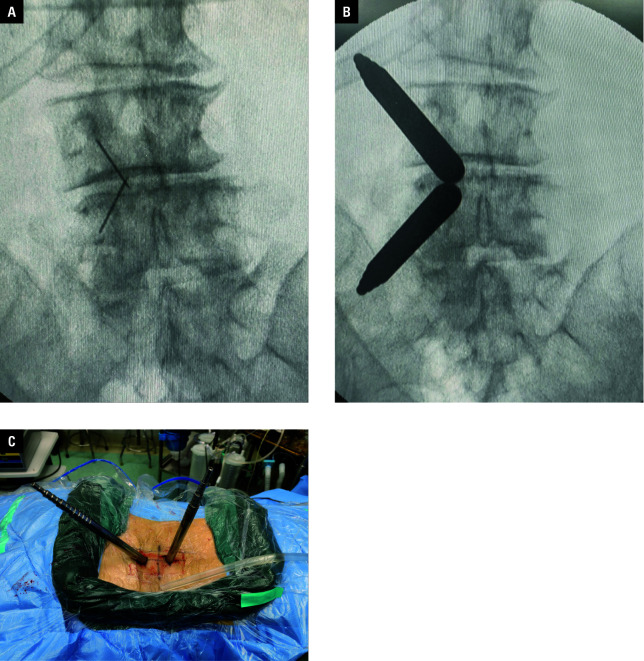

Abstract Image